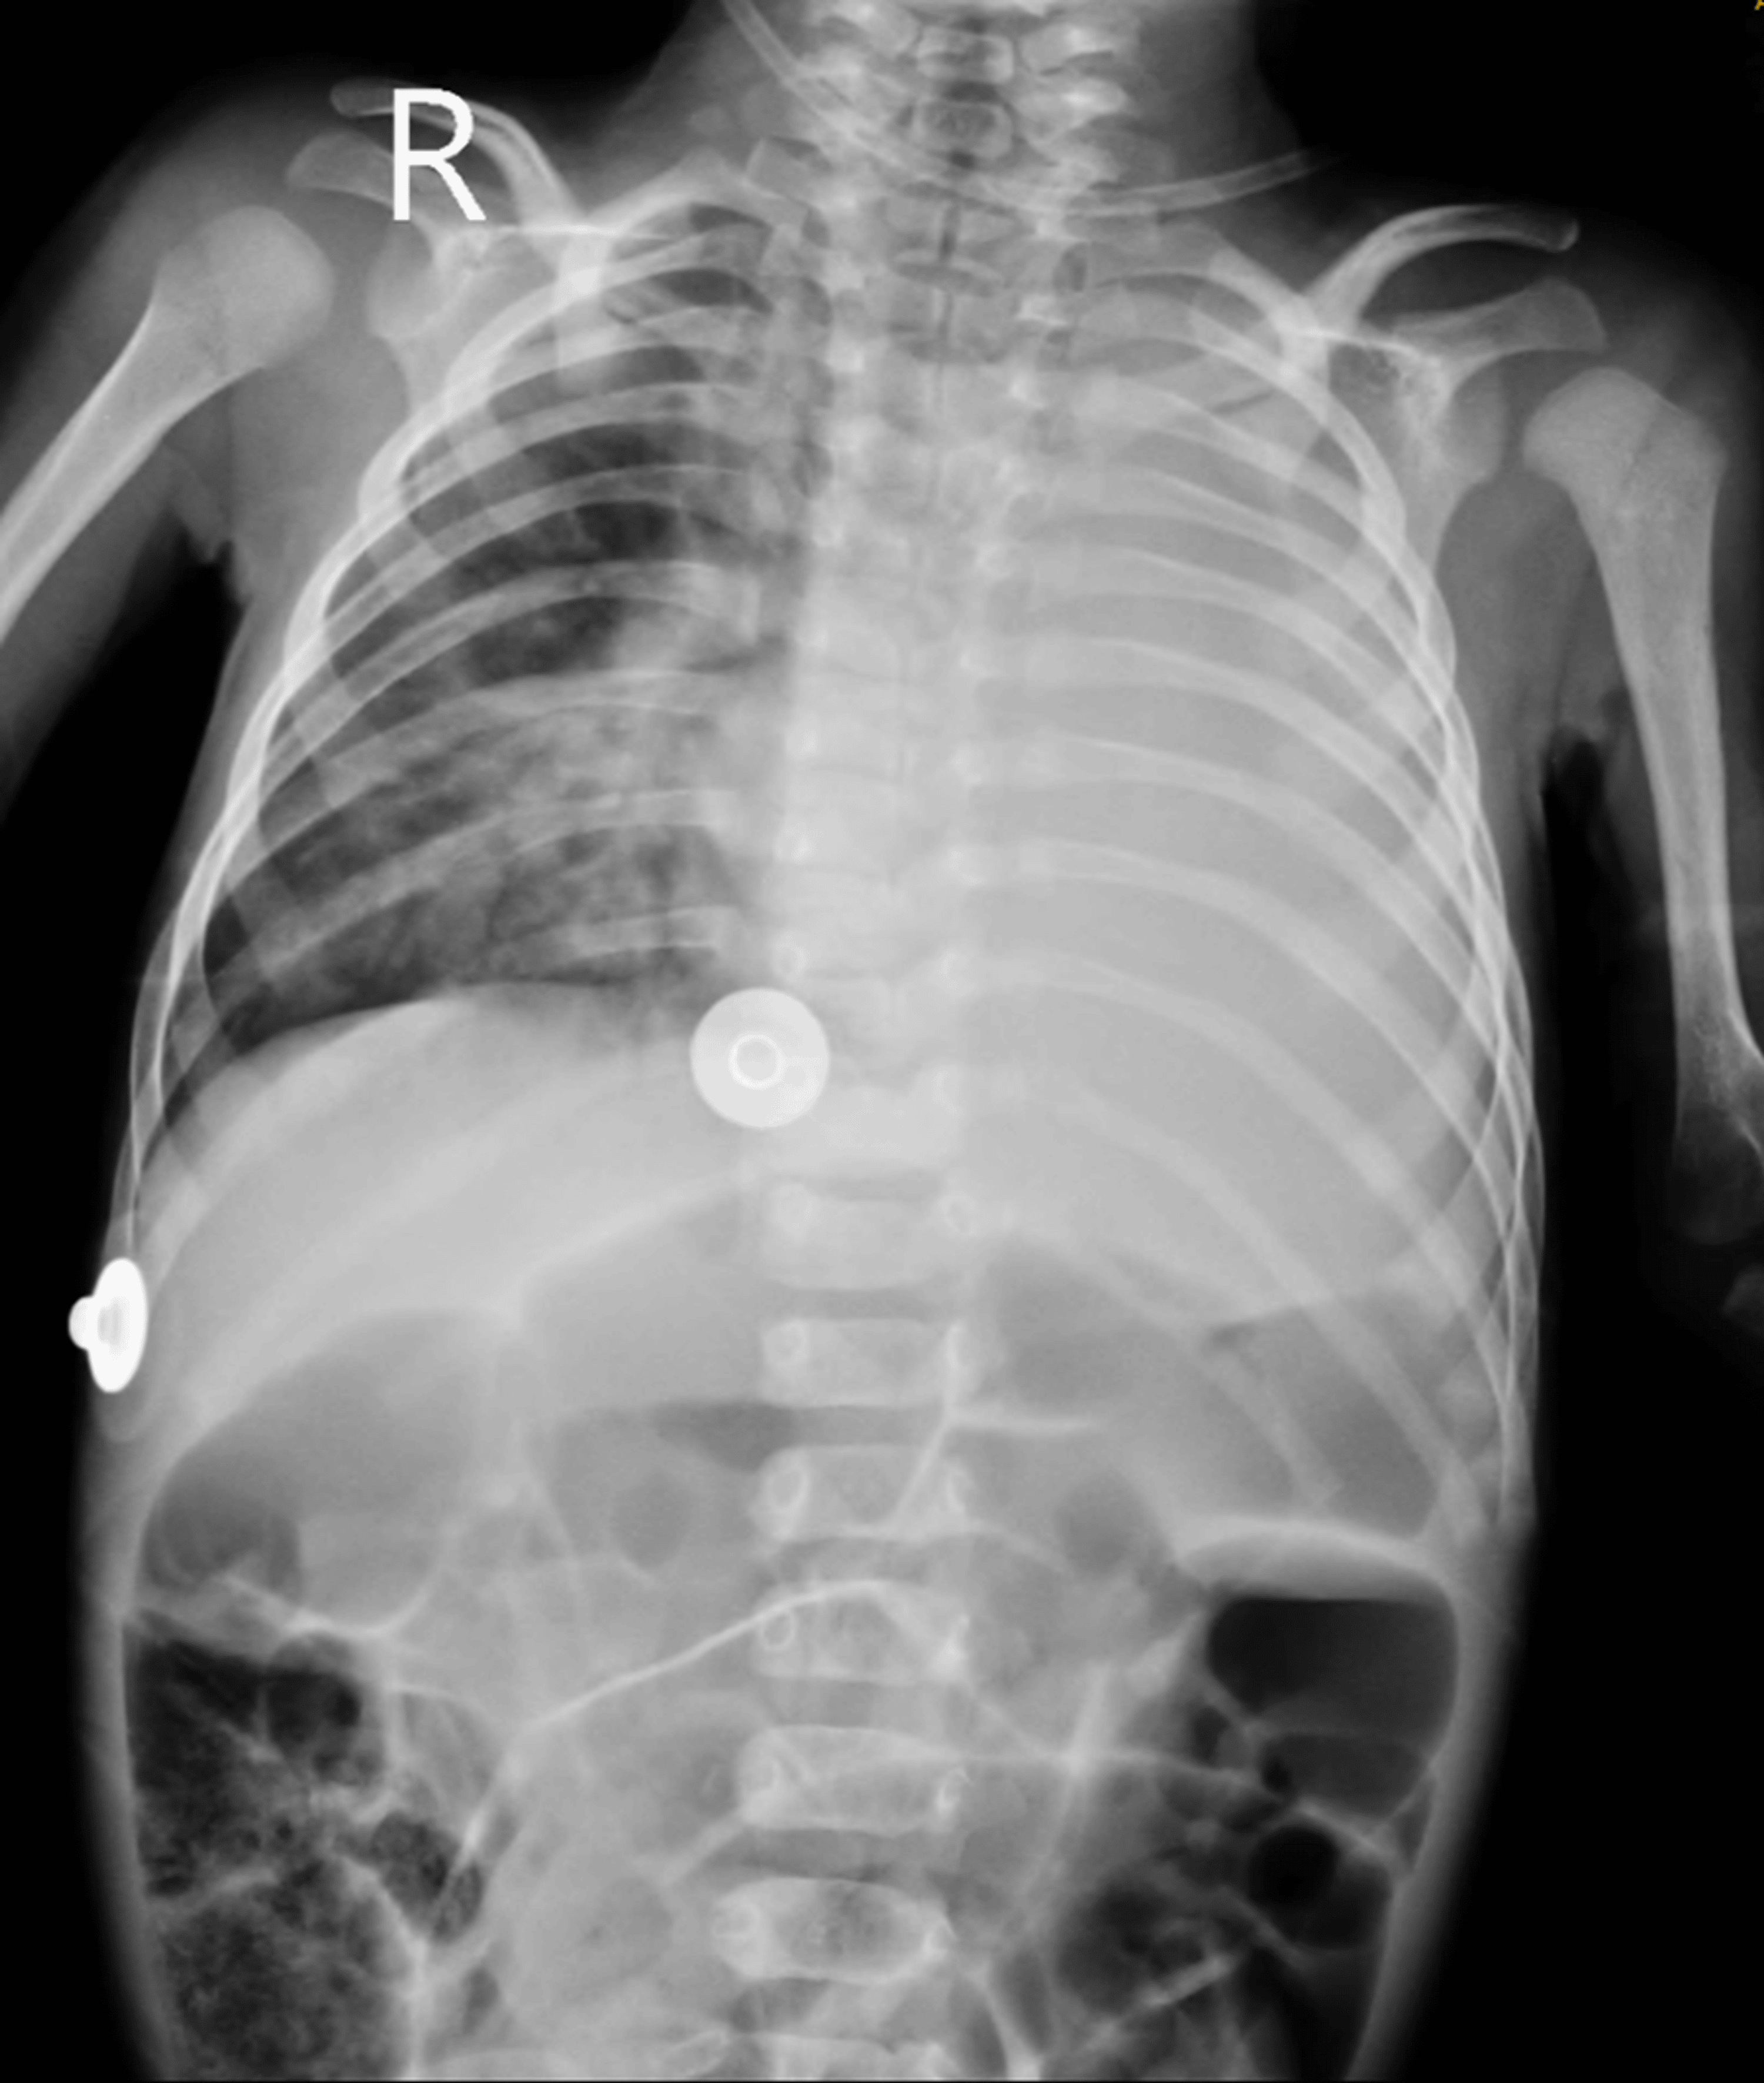

The patient underwent a meticulous pre-anesthetic evaluation, where on examination, he was found to be vitally stable with a pulse rate of 136/min, blood pressure of 80/48mmHg, respiratory rate of 38/min, and oxygen saturation of 98% on room air. His general condition was moderate, but he had severe malnutrition as per the Indian Academy of Pediatrics grading (weight 2.76 kg, length 40 cm). Anticipated difficult airway was diagnosed by retrognathia and short neck. On inspection, chest retractions were present, and on auscultation, a pan systolic murmur was heard (continuous machinery murmur). All the laboratory blood parameters were within normal limits. MRI of the brain revealed ACC with colpocephaly and an arachnoid cyst in the right retro-cerebellar region. Additional findings noted in the ultrasonography of the abdomen and pelvis were gall bladder calculi suggestive of cholelithiasis, splenomegaly (6.1cm), and cystitis in the urinary bladder. Chest radiography showed diffuse haziness in bilateral lung fields (Figure 1).

The patient was weaned off the ventilator and extubated the next day successfully, subsequently shifted to the pediatric intensive care unit (PICU), and handed over to a pediatric resident for further management. The patient received a unit of packed red cell transfusion in the PICU postoperatively. Follow-up chest radiography showed bilaterally clear lung fields with the PDA Amplatzer device (Abbott, Green Oaks, IL) in situ. He improved symptomatically and was discharged. The patient is doing well at home as per the last follow-up (Figure 3).